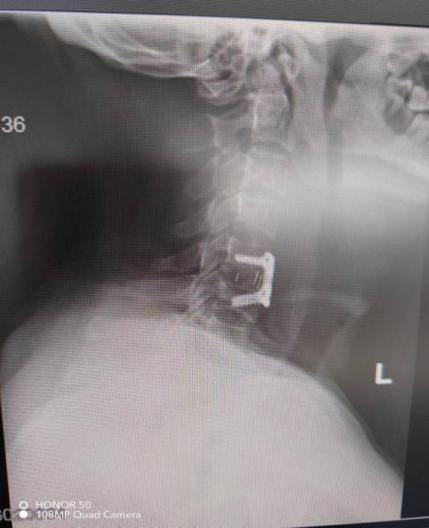

近期,年轻的阿明突然出现一侧肢体无力,开始家人以为“脑中风”,后明确原来为颈椎病椎间盘急性脱出,在广东省人民医院(下称“省人医”)帮扶下,我院骨科予以手术治疗,效果良好,手术后3天顺利出院,患者及家属对医生表示了由衷的感谢!